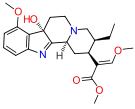

Opium alkaloids and derivatives

Opium alkaloids

Phenanthrenes naturally occurring in (opium):

Semi-synthetic alkaloid derivatives

- Buprenorphine

- Etorphine

- Hydrocodone

- Hydromorphone

- Oxycodone (sold as OxyContin)

- Oxymorphone